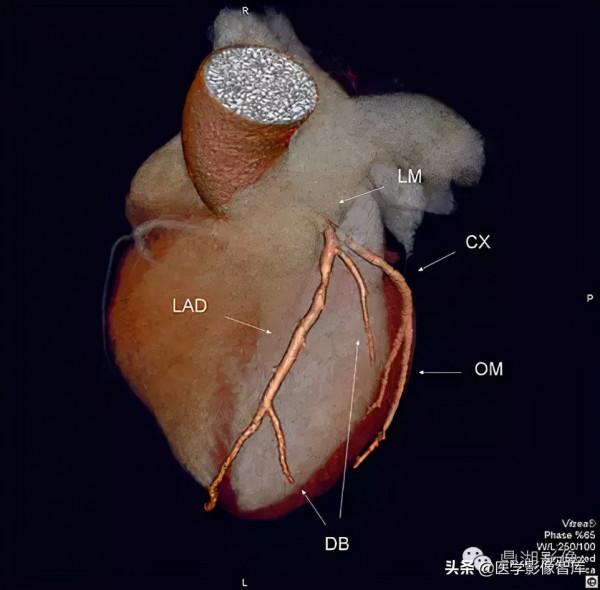

冠脈解剖:

後降支posterior descending branches PD

左室後支 posterior branches of leftventricular PL

銳緣支 right marginal branch AM

右圓錐支 right corus artery CA

右室前支 right anterior ventricular branches

右房動脈 right atrial artery

左冠狀動脈

左主幹 left main coronary artery LM 或LCA

前降支 left anterior descending branch LAD

對角支 diagonal branches 或左室前支 left anterior ventricular branches

前間隔支 anterior septal artery

左圓錐支 left corus artery LCA

左迴旋支 left circumflex branch LCX

鈍緣支 obtuse marginal branch OM

左室前支 left anterior ventricular branches

左室後支 left posterior ventricular branches

左房支 left anticular branches

Maximum intensity projection (MIP)

心肌梗死好發部位為左心室前臂心尖部室間隔前2/3。

心肌梗死的好發部位依次為:

①左冠狀動脈前降支所支配的區域,即左室前壁、心尖部、室間隔前2/3部位。

②右冠狀動脈所支配的區域,即左室後壁、室間隔後1/3及右心室。

③左冠狀動脈迴旋支所支配的區域。即:左室側壁。

Course of LAD

Axial CT slide

Left Coronary Artery System

Right Coronary Artery System

Maximum Intensity Projection (MIP)右圓錐支(CB)